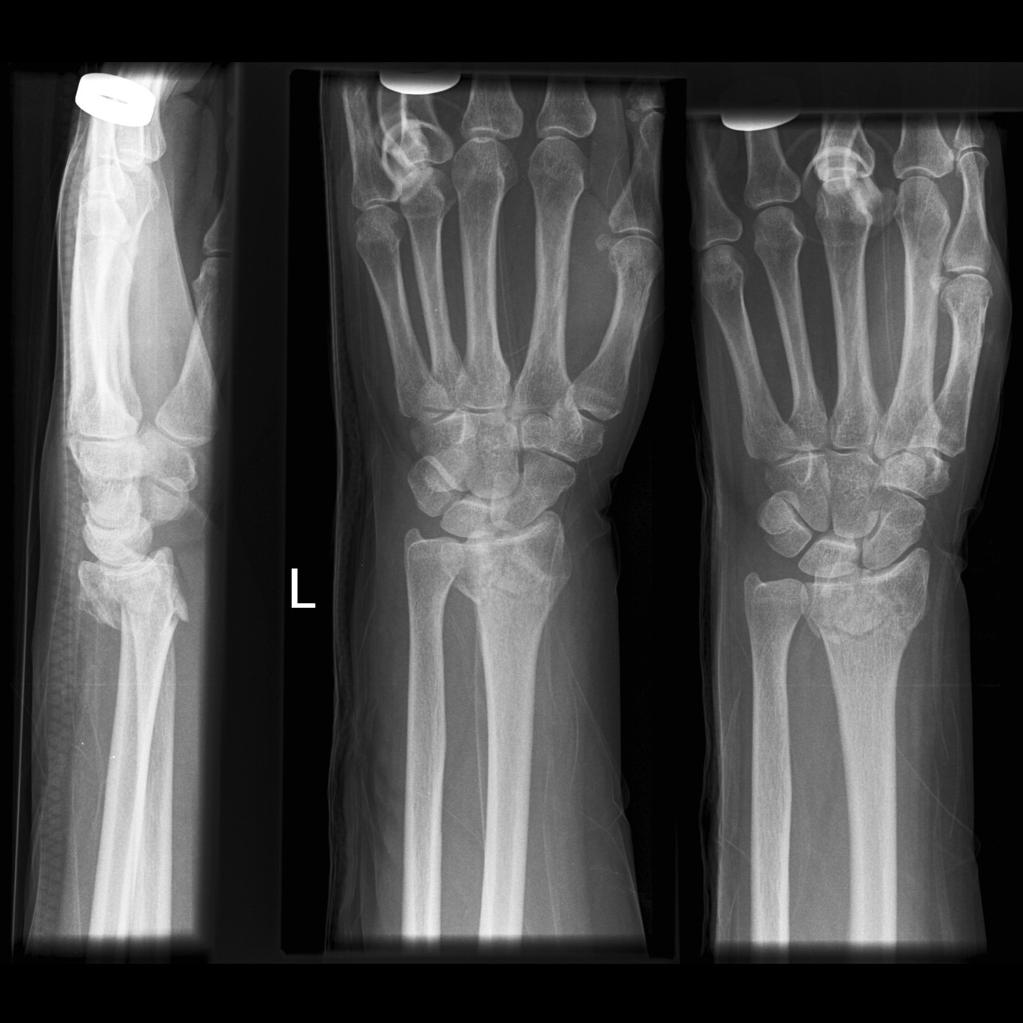

कॉल’स फ्रैक्चर को डिस्टल रेडियस फ्रैक्चर भी कहा जाता है। टूटी हुई कलाई ही कॉल’स फ्रैक्चर है। टेक्निकली, कॉल’स फ्रैक्चर फोरआर्म की दो हड्डियों के बड़े हिस्से में एक हुई ब्रेक है। इसका नाम कॉल’स फ्रैक्चर उस सर्जन के नाम पर पड़ा है ,जिसने सबसे पहले इसका वर्णन किया है। कॉल’स फ्रैक्चर एक आम फ्रैक्चर है, जो पुरुषों की तुलना में महिलाओं में अधिक बार होता है। वास्तव में, यह 75 वर्ष की आयु तक महिलाओं में यह समस्या आम है।

यह सुनिश्चित करने के लिए कि आपकी कलाई सामान्य रूप से ठीक हो रही है या नहीं, नियमित रूप से एक्स-रे कराएं।